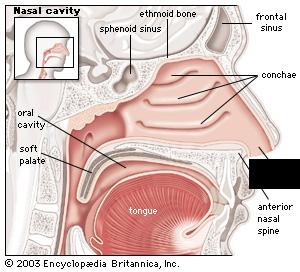

Hard/soft palate

Inferior/middle/superior concha (s.) conchae (pl.)

Nasal Cavity

Nasal septum

Naso/oro/laryngo-phraynx

Oral Cavity

Paranasal sinuses

Tongue

Uvula

Vestibule (of nasal cavity)